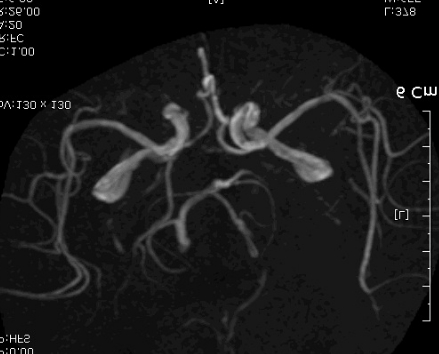

PCA terrotory infartion + AchA territory

촬영 결과는 좌측의 corona radiata, Lt temporal lobe는 anterior choroidal artery 영역입니다.

사진에는  left PCA distal 이후가 보이지 않습니다. (맞나요..?)

일단 pca 영역에 A to a or cardioembolism 생각할 수 있습니다.

좌측사진은 PCA 영역. 우측사진은  AchA 영역의 post. periventricular corona radiata (Stroke 4ed p199, Fig 9-3 과 동일)